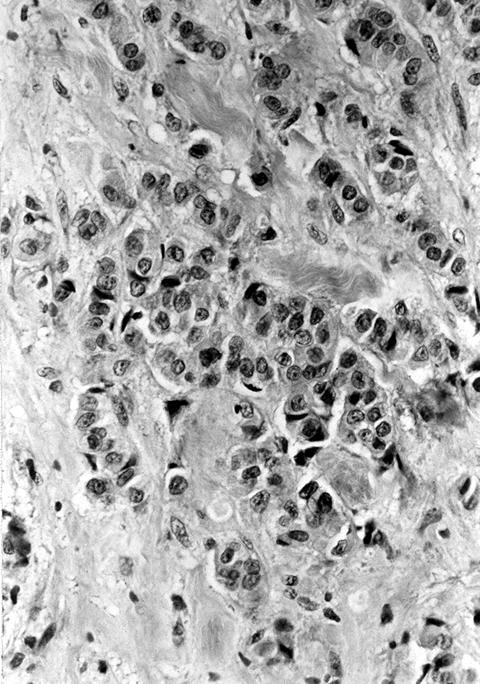

Microscopic (histologic) description

- Wide variety of morphology, can mimic any other thyroid malignancy

- Round, plasmacytoid, polygonal or spindle cells in nests, cords or follicles; often mixtures of these cells

- Round nuclei with finely stippled to coarsely clumped chromatin and indistinct nucleoli, occasional nuclear pseudoinclusion

- Eosinophilic to amphophilic granular cytoplasm due to secretory granules

- Generally low mitotic figures

- Stroma has amyloid deposits from calcitonin, prominent vascularity with glomeruloid configuration or long cords of vessels (Am J Surg Pathol 1995;19:642), coarse calcifications, occasional psammoma-like bodies

- Often angiolymphatic invasion

- Occasionally marked neutrophilic infiltrate, oncocytic tumor cells, papillary patterns

Microscopic (histologic) images

Contributed by Shuanzeng Wei, M.D., Ph.D., Joseph Christopher Castillo, M.D. and Mark R. Wick, M.D.

AFIP images

Images hosted on other servers: